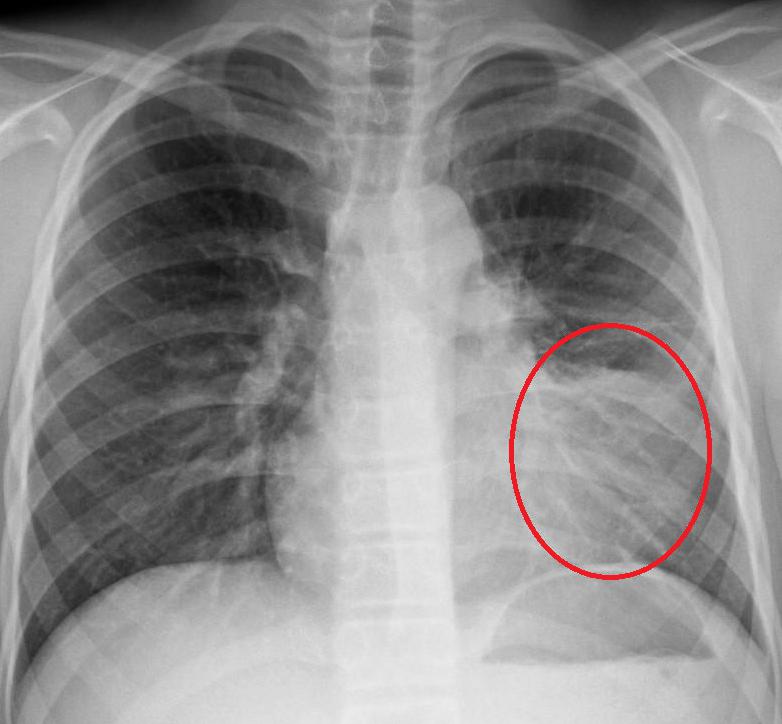

Правда ли, что обязательно нужен контрольный рентген?

В.Ш.: В классической форме пневмонии при амбулаторном лечении рентген не нужен. Тем более, как правило, рентгенологическое выздоровление запаздывает от клинического. Порой рентгенологическая инфильтрация может держаться месяц. Поэтому повторный рентген, выполненный через неделю, или через две, через три, может выявить инфильтрат, который, скорее всего, заставит врача назначить еще один антибиотик. И таким образом, пациент получит лишний курс антибиотиков, который в свою очередь, может пагубно сказаться на его здоровье.

Контрольный рентген нужен, только если у нас что-то идет не так. Если пациент не выздоравливает, мы не видим положительной динамики или нам не нравится течение болезни, тогда мы делаем рентген снимок.

Медицинские показания к проведению рентгенографии легких в двух проекциях (передняя, боковая) включают в себя подозрение на пневмонию при наличии следующих симптомов у пациента:

- Лихорадка выше 38°С с острым началом заболевания.

- Кашель с мокротой любого характера (от слизистой до гнойной с прожилками крови).

- Наличие аускультативных и перкуторных симптомов пневмонии: влажные хрипы, крепитация, укорочение тона.

- Изменения в общем анализе крови по типу лейкоцитоза с цифрами выше 10*109/л либо наличие палочкоядерного сдвига выше 10%.

При выявлении патологических изменений на рентген-снимке, характерных для пневмонии, пациенту назначается соответствующая терапия.

Как определить, что пневмония побеждена, если больной продолжает кашлять? Для этого необходимо сделать рентгеновский снимок легких. Иногда остаточные явления после пневмонии на рентгене наблюдаются как незначительные затемнения на легких. Их можно хорошо разглядеть на пленке.